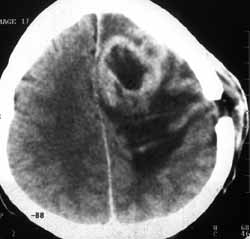

Рис. 7 и 8. Слева - в левой лобной доле два сливающихся кольцевидных образования с выраженным перифокальным отеком - метастазы рака легкого, ошибочно принятые за абсцессы.